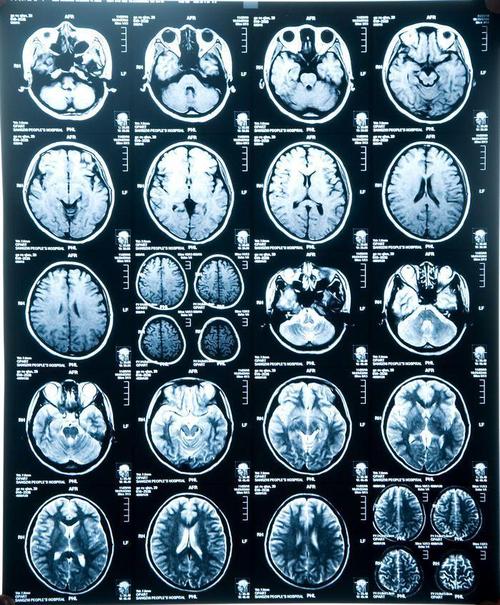

轻度脑萎缩,脑萎缩吃什么药最好

其他无明显症状,这是去检查脑部的影像,医生诊断脑萎缩.请懂的帮忙

脑萎缩ct

脑萎缩核磁

脑萎缩图片

脑萎缩ct表现

脑萎缩图片对比

脑萎缩ct图片

脑萎缩的ct表现及图解

脑萎缩ct片子图片

脑萎缩ct图片解说